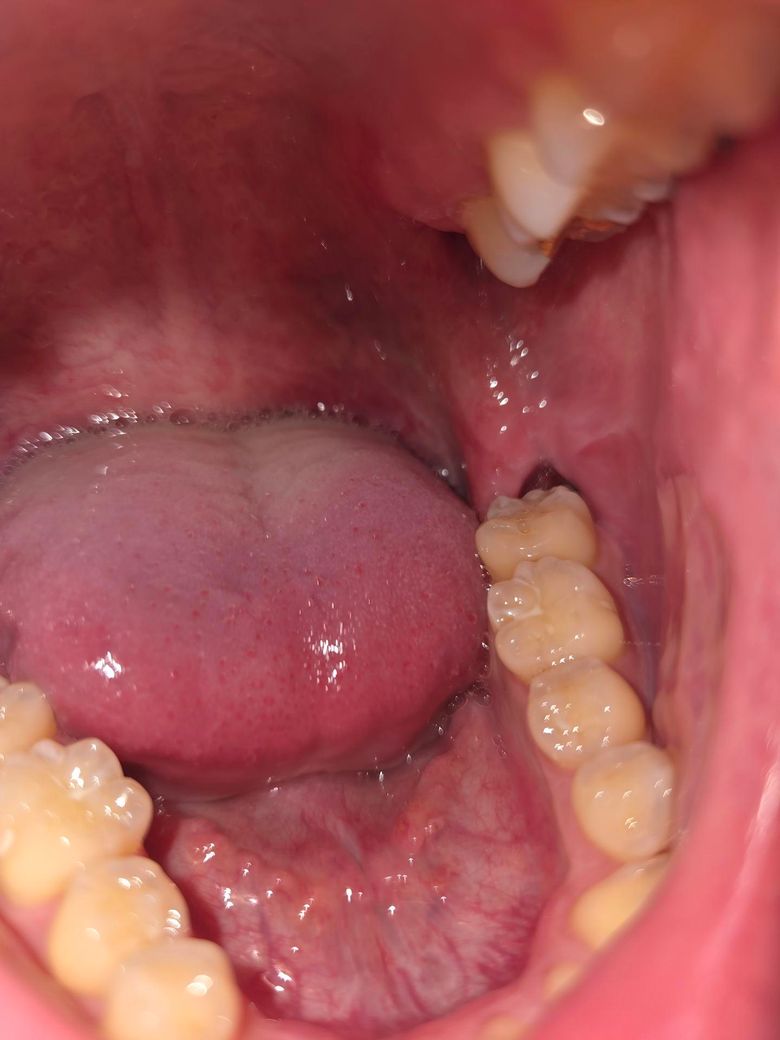

사진상으로 오른쪽에 발치 부위가 있는게 2주 전에 사랑니 발치한 곳이고, 왼쪽에 있는게 1주 전에 발치한 곳입니다. 그런데 2주 전에 발치한 곳은 구멍이 커보이고, 1주 전에 발치한 곳은 구멍이 작아보여서 혹시 이상있는 것인지 궁금해 질문드립니다. (통증은 없습니다. 워터픽 가장 약한 수압으로 하는데도 통증은 없습니다.)

• 1번 째 사진